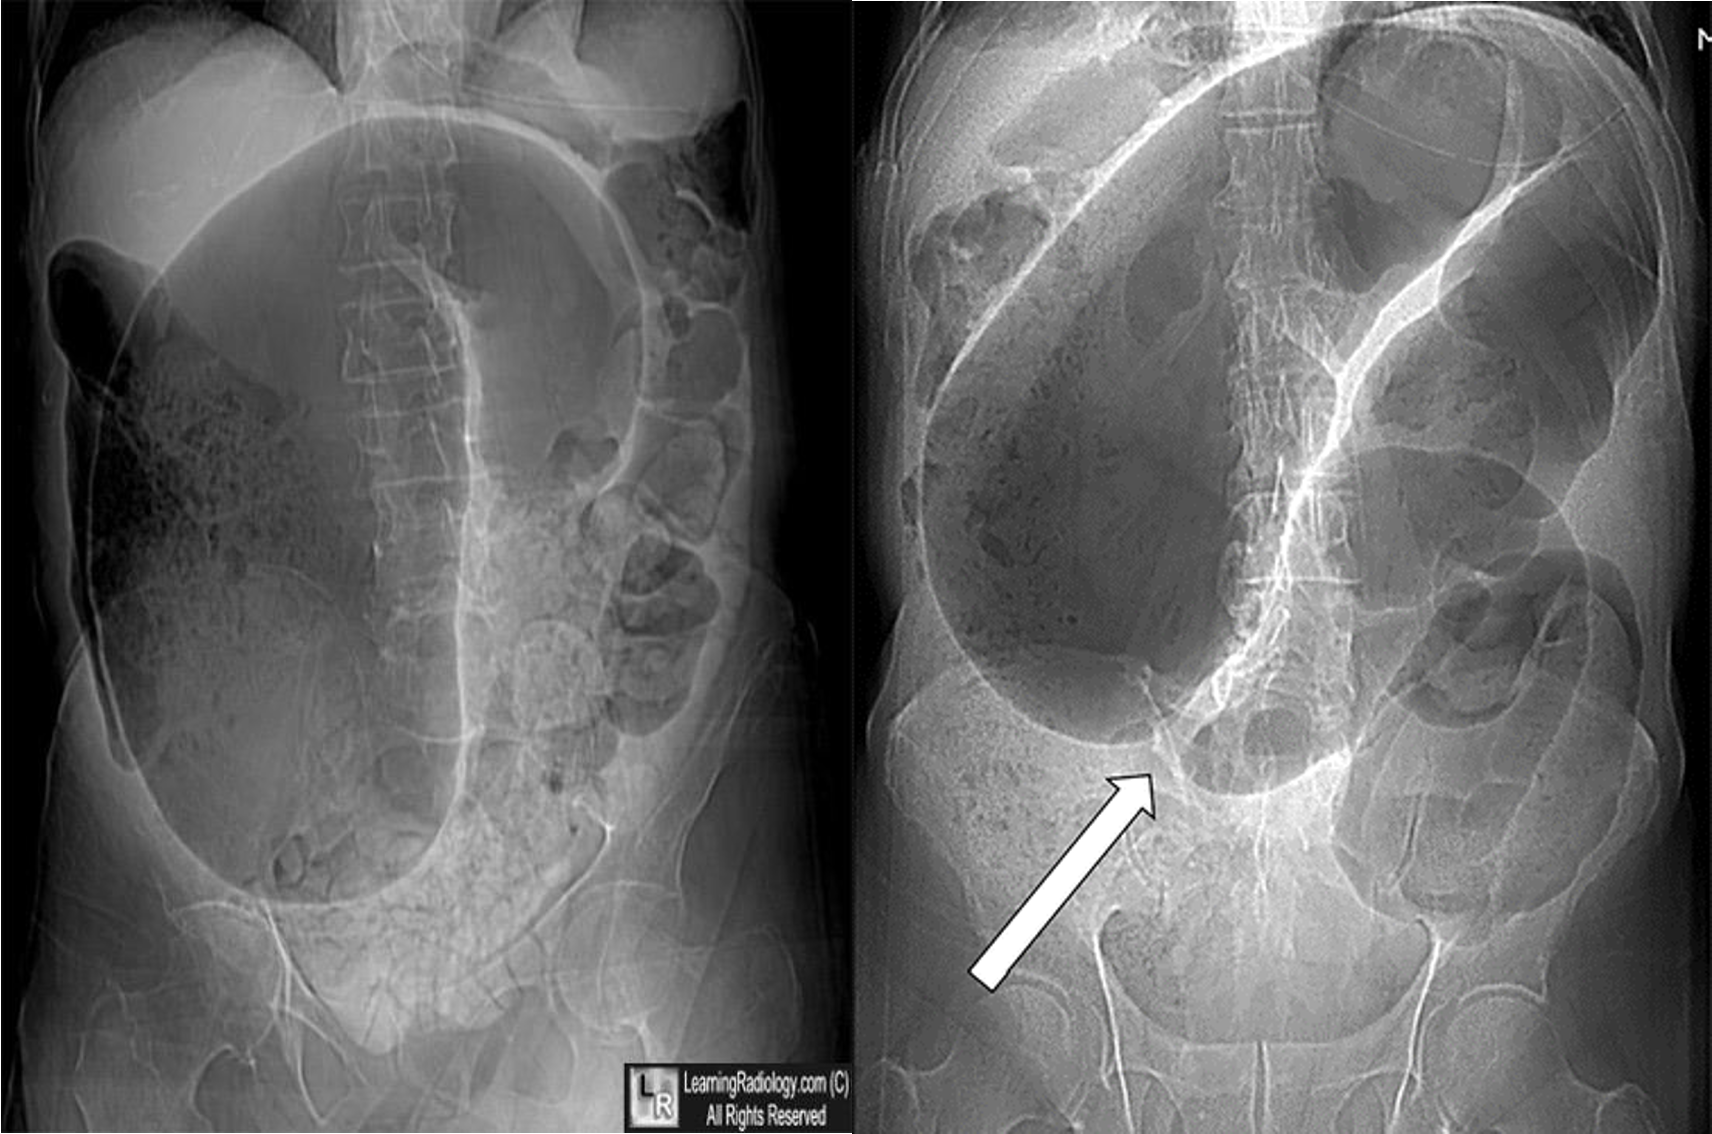

- coffe bean - omega sign - volvulus twisting around its axis - it is closed loop obstruction very dangerous - (treat clonoscopy decompression)

- volvulus